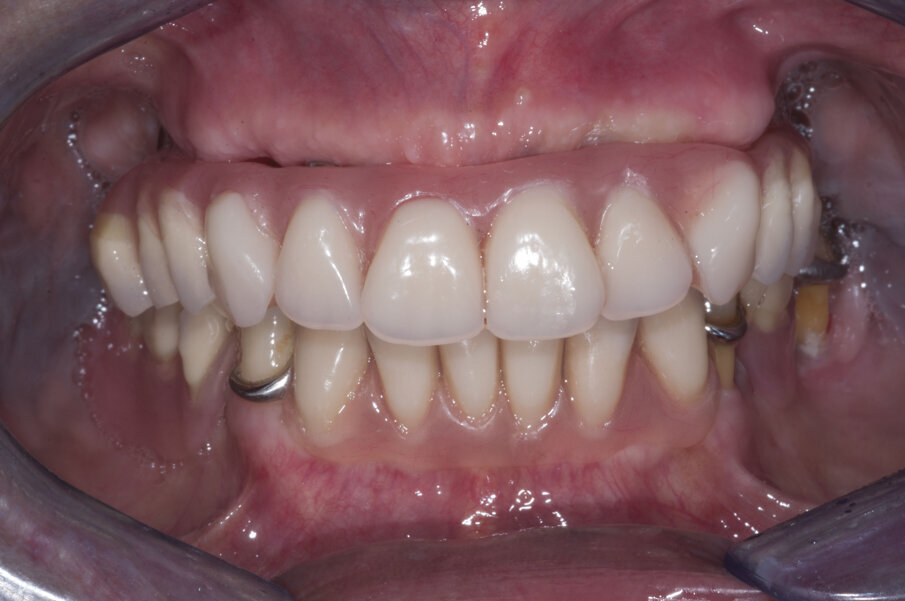

La paziente A. S. di anni 67 si presentata in visita richiedendo la sostituzione della protesi totale superiore con una nuova protesi, possibilmente fissa (Figg. 1-3). Essendo l’anamnesi negativa si è proceduto allo studio e alla pianificazione del caso. La paziente si è presentata con una OPT delle arcate dentarie (Fig. 4) che evidenziava un’ottima quantità di osso alveolare residuo. Dopo esame intra- orale si prescrive una CBCT per poter pianificare nel dettaglio la chirurgia implantare.

Il primo passo per riabilitare la paziente è stato comunque la sostituzione della protesi totale con una nuova più congrua, questo ha portato alla correzione sia della classe scheletrica non corretta che della VDO, fonte di disagio e sofferenza. L’esame extra-orale evidenziava questo dettaglio e come questo influenzasse il sorriso della paziente (Figg. 5-7).

La nuova protesi totale provvisoria ha portato immediatamente un miglioramento funzionale ed estetico, con un notevole beneficio psicologico sulla paziente ed un enorme vantaggio per il prosieguo della terapia (Figg. 8-10). Il nuovo montaggio con denti di maggiori dimensioni ed una differente occlusione ha conferito un miglior supporto al labbro superiore ed una migliorata estetica del sorriso (Fig. 11). Alla luce della nuova situazione, accettata e gradita dalla paziente, si è incominciato a pianificare la procedura chirurgica. Avendo la CBCT evidenziato dei volumi ossei adeguati (Fig. 12), si è proceduto allo studio del caso mediante un software di chirurgia guidata (Simplant, Dentsply-Sirona) (Figg. 13, 14).

Verificata la precisione del lavoro si procede alla consegna. La Fig. 38 evidenzia la perfetta salute dei tessuti peri-implantari a protezione dei MUA, e nelle figure 39 e 40 evidenziano l’ottimo adattamento del manufatto finale ai tessuti intra ed extra-orali. La panoramica di controllo a 12 mesi dal completamento del lavoro evidenzia una perfetta stabilità dei livelli ossei dopo il carico protesico (Fig. 41).